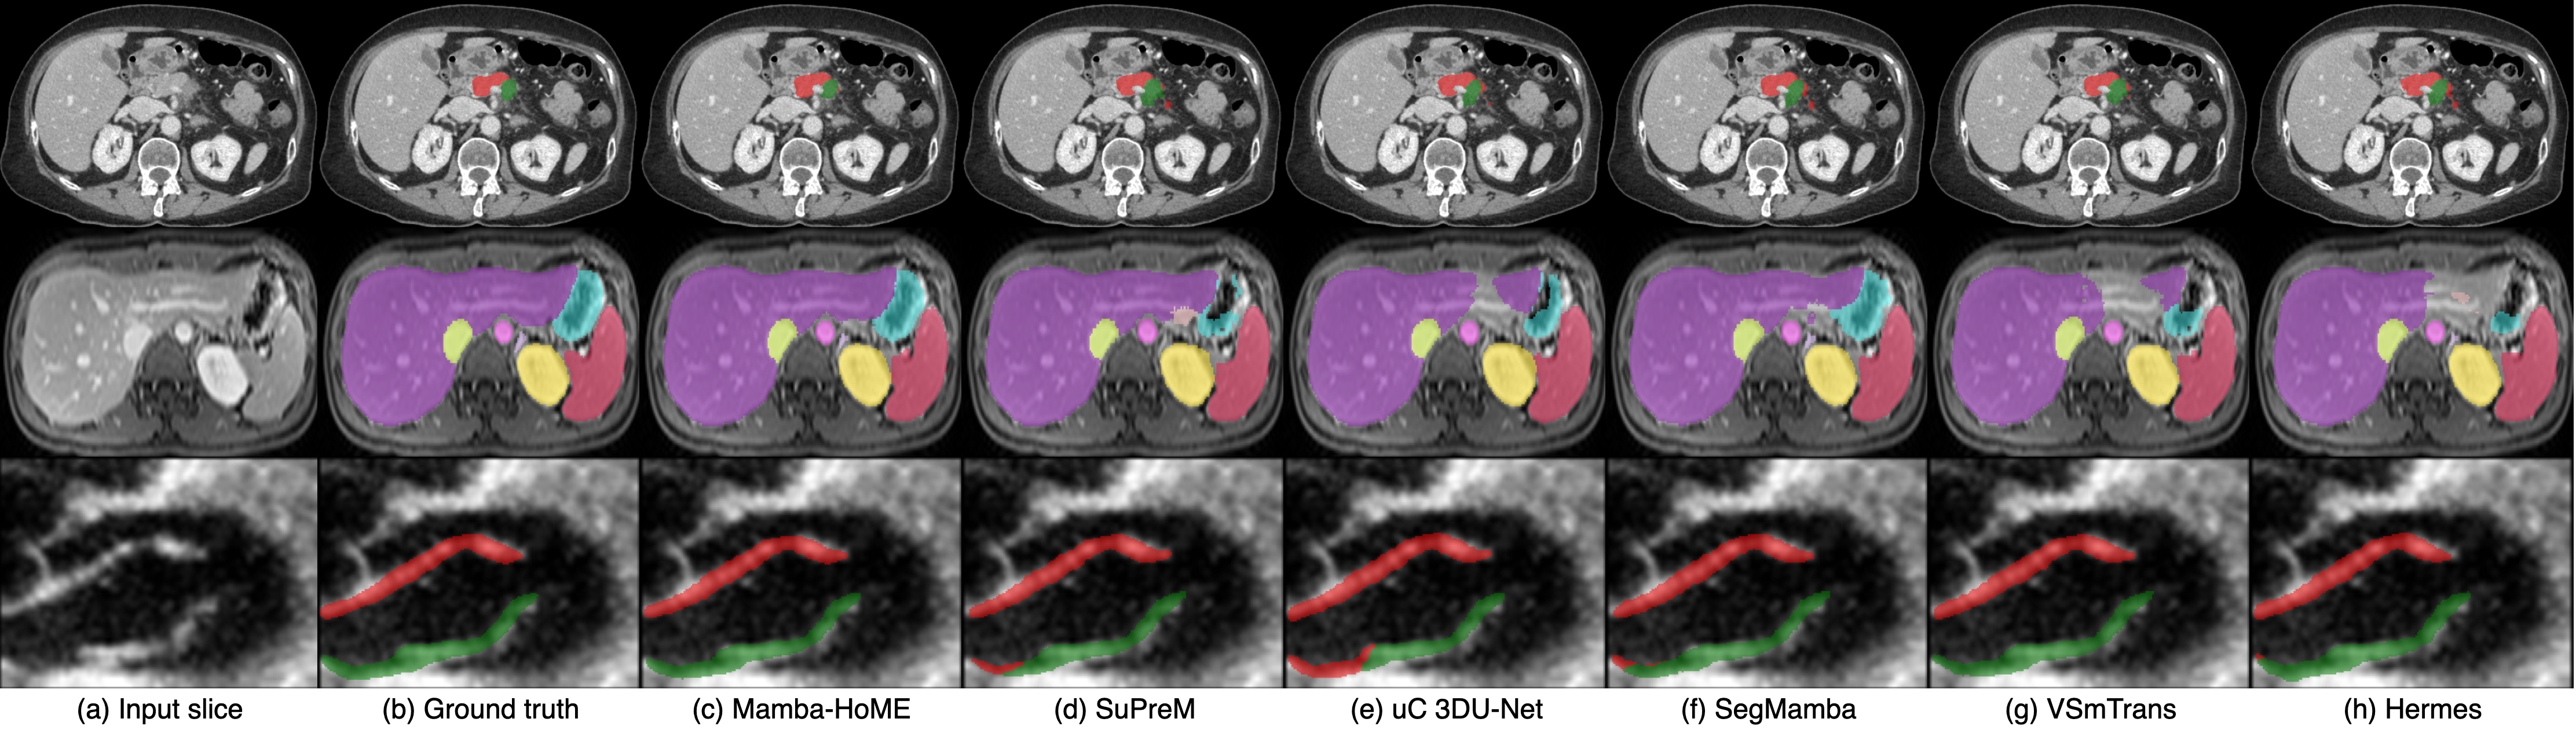

Qualitative results. Figure 2 presents a qualitative comparison of our proposed Mamba-HoME method against the five top-performing baselines across three primary 3D medical imaging modalities: CT, MRI, and US. These modalities exhibit different organ contrasts, noise levels, and resolutions. Mamba-HoME demonstrates consistent improvements in segmentation quality across these scenarios. In the first row, it effectively handles small and closely located structures, showing precise boundary delineation while reducing common artifacts seen in baseline predictions. The second row highlights its capability to accurately segment organs of various shapes and sizes, even under low image quality conditions, with reduced susceptibility to over- or under-segmentation. The third row illustrates Mamba-HoME’s robustness in handling noisy and low-resolution data, maintaining clear and anatomically accurate boundaries.

Figure 2: Qualitative segmentation results from top to bottom: CT, MRI, and 3D US. From left to right, each column shows the input slice, ground truth, the proposed Mamba-HoME, and the five next best-performing methods.